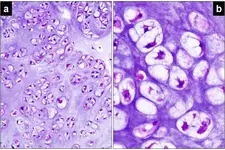

3. Tanı Yöntemleri Diz kıkırdak aşınması tanısı, klinik muayene ve görüntüleme yöntemleri ile konulmaktadır. Bu yöntemler arasında: